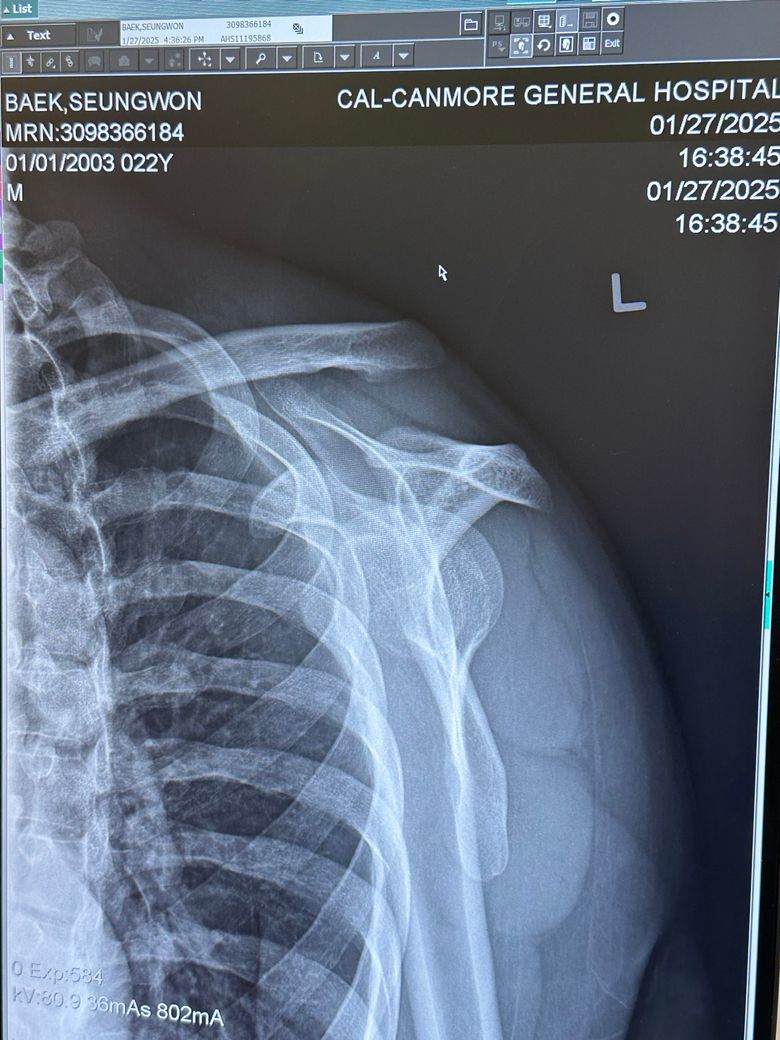

어깨 이거 문제 없이 괜찮은건가요??

캐나다에서 스키타다 심하게 넘어졌습니다 어깨가 안 움직이길래 바로 병원으로 왔고 익스레이도 촬영했습니다 여기 캐나다 병원에서는 문제가 없고 붕대로 감고 있으면 된다고 하면서 설명하기를 나라마다 치료하는 게 다르므로 한국 병원에 다시 가보라고 합니다 아직 여행 일정이 남아 다음주 귀국 예정인데 캐나다 의사선생님 말대로 그냥 붕대만 해도 문제가 없을까요? 캐나다 의사선생님을 믿지 못하는 것이 아니라 한국에서 치료를 받지 못하고 있자니 제 마음이 불안해서 확실하게 알고 싶습니다

• 4번 째 사진

지금 어깨 관절의 뼈 정렬이 좋지 않스니다. 엑스레이 상 보시면 쇄골과 견갑골이 서로 간격이 많이 벌어져있습니다. AC JOINT 라고 해서 쇄골과 견갈골 견봉과의 간격이 너무 벌어져있습니다. 그쪽 인대가 늘어났던지 아니면 삼각근이나 어깨 안정화 시켜주는 근육이 손상을 입은것으로 보입니다. 저런 경우에는 디테일하게 초음파 촬영을 해서 인대에 문제인지 아니면 힘줄에 문제인지를 보고 그에 따른 약물치료나 주사치료를 하면 좋겠지만, 현재 병원에서 하실 수 있는게 고정(붕대)이시면 어깨뼈를 최대한 안정적으로 고정해주시는게 지금 상황에서는 현명한 대처법으로 보입니다. 스키타다가 넘어지면서 AC JOINT라는 관절의 문제가 생긴것으로 보이는데, 일단 인대가 파열이나 끊어진게 아니면 고정 방법으로 해서 연부조직의 자가적인 회복을 기대해볼 수도 있습니다. 우선은 그렇게 해주시는게 좋을거 같습니다.